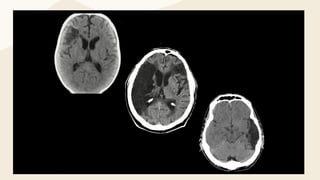

Signos Inmediatos

El primer signo visible en la TC es la hiperdensidad en un segmento de un

vaso. Representa la visualización directa del trombo / émbolo

intravascular y, como tal, es visible de inmediato

se observa con mayor frecuencia en la arteria cerebral media (ACM).

Cuando se observa hiperdensidad sobre el segmento M1 de la ACM se

conoce como el signo de la ACM hiperdensa o signo de la cuerda. Si se

encuentra en un ramo de la arteria, en la fisura silviana, se denomina signo

del punto.

Ictus Hiperagudo Temprano

se pueden observar signos tempranos de isquemia en

aproximadamente el 60% de los casos dentro de las 2 horas del

inicio de los síntomas y más del 80% de los casos dentro de las

6 horas.

Los signos visibles dependen del sitio de la oclusión y la

presencia de flujo colateral.

Los primeros hallazgos incluyen:

Pérdida de la diferenciación entre sustancia gris y blanca.

Hipodensidad de los núcleos basales

Hipodensidad cortical con borramiento giral